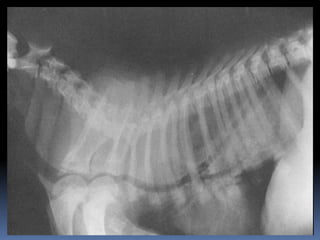

Hey Dr., no puedo orinar

Hey Dr., nopuedo orinar